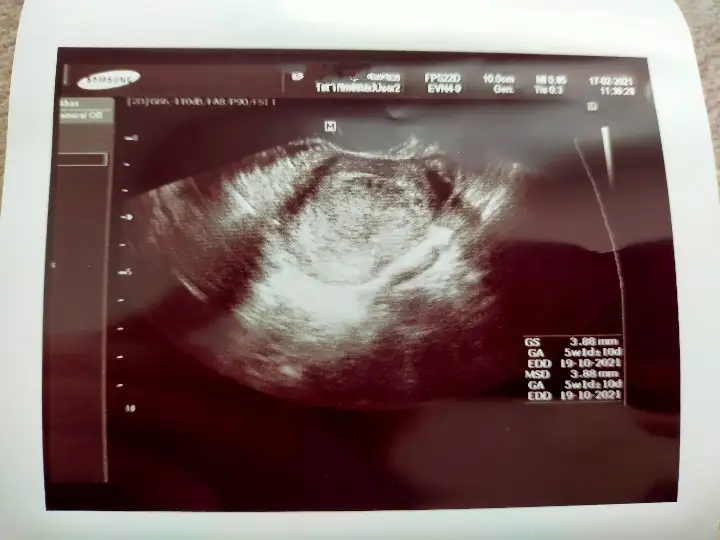

Kese 4 mm yakın ölçmüş ama ben ölçüm çentiğini göremedim canım. Kesenin etrafı iyi kalınlaşmış aslında. Günü için de 5+1 demiş ama kese 4 mm iken 5+1 olamaz. Onu nasıl hesaplamış cihaz anlamadımBilmiyorum ki canım kaç olmadı gerektiğini Dr bı kızardı bozardi zaten bende birşey soramadım yarın tekrar gel dedi

Kese 4mm iken kaç haftalık olur 4mu evet çentikli değil ne biliyom nasıl ölçtü kesenin etrafının iyi kalınlaşması nedir ben zaten hiç birşey anlamadım keseyi gorecem diye zaten aleti içimde bı ora bı bura gezdirdi canımda yandı saklanmış dedi anlamadim dış gebelik olabilirmi?Kese 4 mm yakın ölçmüş ama ben ölçüm çentiğini göremedim canım. Kesenin etrafı iyi kalınlaşmış aslında. Günü için de 5+1 demiş ama kese 4 mm iken 5+1 olamaz. Onu nasıl hesaplamış cihaz anlamadım![]()

Yok ya ben gördüm. sağda yukarda. Yani etrafı iyi kalınlaşmış demek iyi tutunmuş. 4 mm kese tam kaçıncı güne tekabul eder bilmiyorum canım ama 5+1'den ufaktır.Kese 4mm iken kaç haftalık olur 4mu evet çentikli değil ne biliyom nasıl ölçtü kesenin etrafının iyi kalınlaşması nedir ben zaten hiç birşey anlamadım keseyi gorecem diye zaten aleti içimde bı ora bı bura gezdirdi canımda yandı saklanmış dedi anlamadim dış gebelik olabilirmi?

Cemin asistanı dedi dış gebelik olabilir diye.E şimdi benim sağ tarafımamı yerleşmiş oluyor geç döllenme mi ne ya off valla bunaldım Dra yarın iyi bı sorayım unutmazsam heyecandan 1gunde ne kadar buyuyecekte çağırdı bu kadın beni yaYok ya ben gördüm. sağda yukarda. Yani etrafı iyi kalınlaşmış demek iyi tutunmuş. 4 mm kese tam kaçıncı güne tekabul eder bilmiyorum canım ama 5+1'den ufaktır.